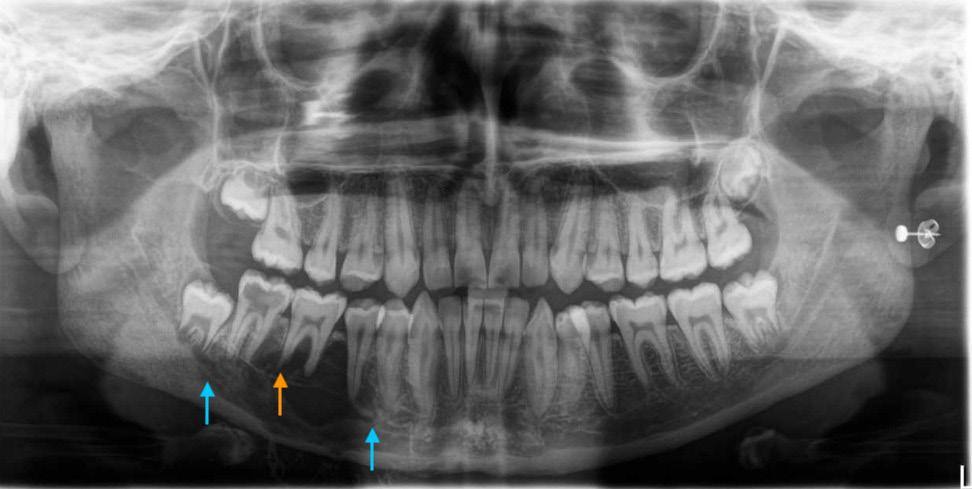

Treatment planning protocol was the same for all individuals and included examination, impressions for study models and a clinical bite record using wax and captured in centric relation (CR, the condyle was in the most superior and posterior position in the glenoid fossa). The clinical bite records and study models were subsequently digitised. A pre-operative medical-grade helical CT image was captured with the individual in a supine position with their lips closed, ensuring gentle occlusion in centric occlusion (CO, the position of maximum intercuspation of the dentition) without a bite registration splint. The CT protocol was derived from KLS Martin Group (KLS Martin Group, Germany) including special resolution of 0.5–1.25 mm and gantry tilt of 0°. A virtual skull model was created for each individual by a clinical engineer using Materialise Magics three-dimensional printing software (Materialise, Belgium). This process involved two steps with collaboration between the clinical engineer and the surgeon pivotal in forming the surgical plan, a dynamic process tailored to each patient’s unique requirements, outlined in Figure 1

Seventeen individuals (12 females, age range between 18 and 61 years) satisfied the inclusion criteria. The number of patients in each surgery type (maxillary, mandibular, bimaxillary) is presented in Figure 3

The disparities between the anticipated positions of selected landmarks and their actual post-operative locations in both singlejaw and bimaxillary surgeries are summarised in Table 2

For the maxillary surgeries, the mean combined difference between anticipated movements and final position along the x, y and z axes was compared between single-jaw (1.33 ± 1.12 mm) and bimaxillary surgeries (1.33 ± 1.30 mm), as seen in Figure 4. An independent samples t-test revealed no statistically significant difference between single-jaw and bimaxillary surgeries (t(210) = 0.01; P = 0.992). The mean combined difference between anticipated movements and final position along the x, y and z axes in the mandible for single-jaw (1.00 ± 1.20 mm) and bimaxillary surgeries (1.75 ± 1.47 mm) was calculated (Figure 5). An independent samples t-test indicated a significant difference (t(257) = 4.91; P < 0.001; d = 0.54).

Three-dimensional linear measurements ranged between a mean of 0.86 mm for the lower right mandibular molar in single-jaw surgery

and 5.75 mm for the pogonion in bimaxillary surgery. Levene’s test did not reveal any statistically significant difference among the variances of the maxillary landmarks in either single-jaw or bimaxillary surgeries (single jaw: F(5, 84) = 0.53, P = 0.752; bimaxillary: F(5, 138) = 0.37, P = 0.871). However, a significant difference was noted between mandibular landmarks in both single-jaw and bimaxillary surgeries (single jaw: F(8, 88) = 4.85, P < 0.001; bimaxillary: F(8, 207) = 2.96, P = 0.004). A significant difference in variance occurred between single-jaw and bimaxillary surgeries in the mandible (F(1, 322) = 7.93; P = 0.005), but not in the maxilla (F(1, 232) = < 0.001; P = 0.996) and not between the maxilla and mandible in single-jaw operations (F(1, 196) = 2.57; P = 0.110) or bimaxillary operations (F(1, 358) = 1.51; P = 0.220). There was a heterogeneic variance among the x, y and z axes in the maxilla in both single and bimaxillary surgeries (single jaw: F(2, 87) = 6.50, P = 0.002; bimaxillary: F(2, 141) = 6.28, P = 0.002), but not in the mandible (single jaw: F(2, 105) = 0.13, P = 0.883; bimaxillary: F(2, 213) = 0.32, P = 0.729).

This article shows that this simplified method of VSP assessment results in a clinically accurate assessment for orthognathic surgery. The accuracy from the planning protocol is derived from segmentation of the CT imaging to incorporate digitised scanned occlusion. Deviations from this position could pose challenges for clinical engineers in determining the correct condylar position, leading to a notable variance between the planned and actual outcome for CoR

and CoL points. Accurate data collection before formulating the surgical plan, including the capture of impressions and centric relation clinically is crucial, as any errors in this phase would propagate through the planning process. This simplified protocol not only achieves clinically acceptable outcomes but also improves surgical and pre-operative efficiency by reducing technique sensitivity, requiring only one consultation appointment, eliminating the need for guide splints, and streamlining the process with a single preoperative radiographic scan.

Most mean landmark variances, except for three, and all median values except one, remained below the 2-mm threshold recognised as clinically significant.19 The findings of this study demonstrate favourable outcomes in the maxilla, both for singlejaw and bimaxillary surgeries, with greater accuracy of maxillary landmark positions (mean, 1.09–1.51 mm). Therefore the maxillary position on the CT scan is not influenced by the position of the condylar seating at the time of the scan. In contrast, the mandibular movements had greater variations in the accuracy of landmark positioning. Landmarks anterior to the osteotomy in the proximal segment of single-jaw surgery (B, mandibular mid-incisor point [Md], Pog) exhibited minimal variance between their planned and actual postoperative positions (mean, 0.43–0.61 mm). However, the points in the distal segment (CoL, CoR, GoL, GoR, lower left first molar [LLM], lower right first molar [LRM]) had larger discrepancies (mean, 1.21–2.34 mm). Notably, GoL exceeded the 2-mm threshold for clinical acceptability.19 This may be explained by intraoperative seating of the condyle being potentially varied from the predicted seating of VSP; influenced by soft tissues within the temporomandibular joint, perimandibular musculature, alignment of the lower border of the mandible and control of torsional movements of the proximal segment.

During bimaxillary surgery, the mandible exhibited the highest degree of variance, particularly at Pog (2.89 mm) and GoL (2.19 mm) and GoR (1.62 mm). This is expected due to the compounded nature of any discrepancy from the initial maxillary movement and fixation position before mandibular movement. Previous studies